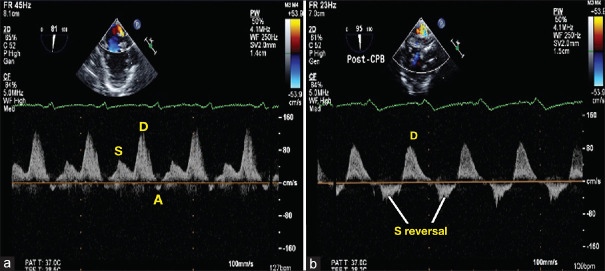

Does an Unrestricted Atrial Septal Defect Alter the Pulmonary Venous Doppler Flow Profile and Downgrade the Severity of Mitral Regurgitation?

不受限制的房间隔缺损会改变肺静脉多普勒血流谱并降低二尖瓣返流的严重程度吗?